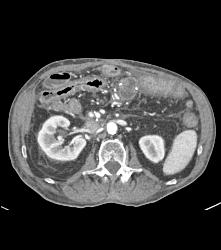

Carcinomatosis on Omentum